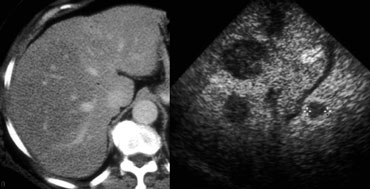

LEFT: Classic US appearance of a hemangioma.RIGHT: Also a hemangioma but now in a hyperechoic liver, so the lesion is relatively hypoechoic. Notice increased sound transmission. LEFT: Classic US appearance of a hemangioma.RIGHT: Also a hemangioma but now in a hyperechoic liver, so the lesion is relatively hypoechoic. Notice increased sound transmission.